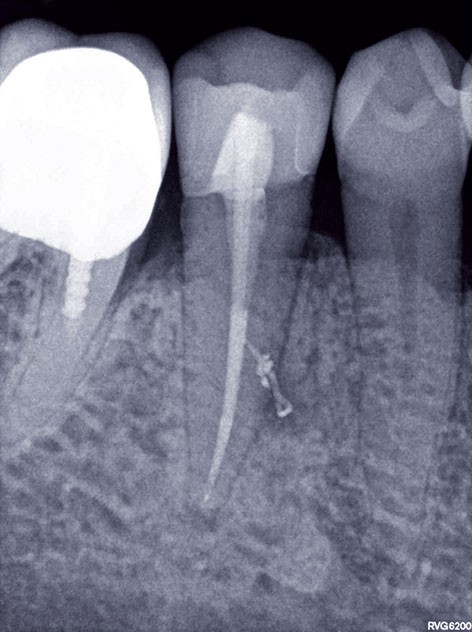

3, 4, 5. La restauration est déposée, les tissus carieux éliminés et la cavité d’accès aménagée avant la réalisation du traitement endodontique. La radiographie postopératoire permet de visualiser l’obturation du canal latéral en regard de la LIPOE.